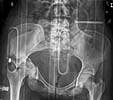

Subject: Pelvic & acetabular fracture

A 19 year old woman fell/jumped from the third floor.

Attached some of the X-rays and CT pictures. Apologizes for the quality of the imaging. What are your recommendations for treatment of the pelvic/acetabular and ankle injury?

Pelvic Xrays - Click to Magnify